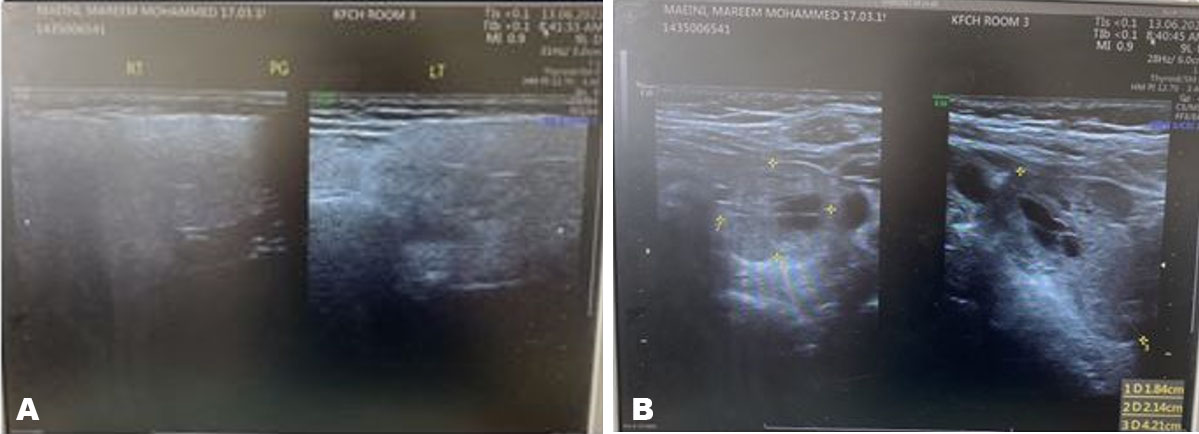

Electrocardiogram (ECG) showed normal sinus rhythm. A neck ultrasound study was done and showed in Figure 1A and Figure 1B.

A large isoechoic left inferior retrothyroid well-defined oval shape mass lesion/nodule measuring about 4.2 × 2.1 × 1.8 cm.

Both thyroid lobes and the thyroid isthmus were average in size with regular outlines, showing homogeneous parenchymal echotexture.

Figure 1: (A) US neck. (B) US neck with parathyroid adenoma localized in left inferior to the thyroid gland.